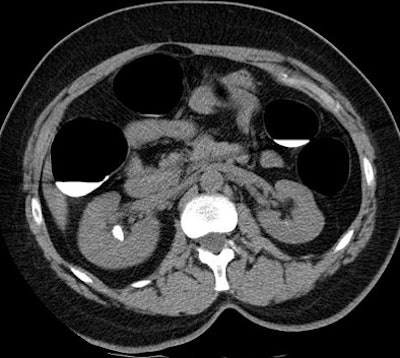

![]() |

| Above, 14-mm right-sided kidney stone detected at virtual colonoscopy. Below, coronal image shows a left lower pole calculus. All images courtesy of Dr. Perry Pickhardt. |